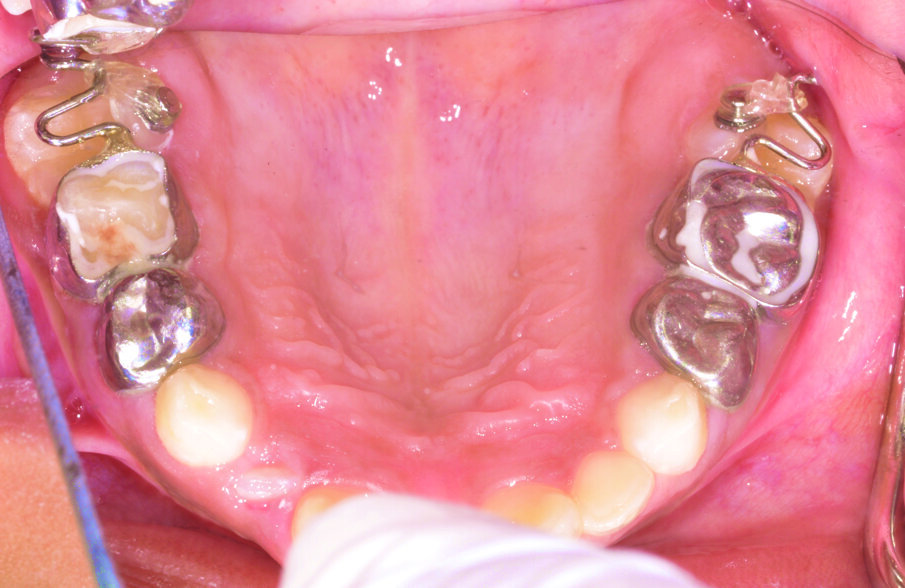

Figure 5: Bilateral ectopic eruption of the upper first permanent molars treated by a sling shot type appliance.

Treatment depends on how severe the impaction appears clinically and radiographically. For mildly impacted first permanent molars, where little of the tooth is impacted under the primary second molar, elastic or metal orthodontic separators can be placed to wedge the permanent first molar distally4, Figure 3. For more severe impactions, distal tipping of the permanent molar is required. Tipping action can be accomplished with brass wires, removable appliances using springs, fixed appliances such as sectional wires with open coil springs, Figure 4, sling shot-type appliance3, Figure 5, a Halterman appliance5, Figure 6, or surgical uprighting6.